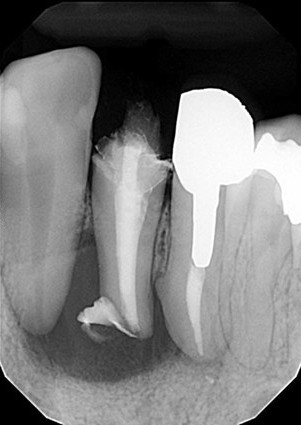

| 主訴 | 膿がたまてしまっていて痛い状態 |

| 状態 | 歯をとった瞬間に黄色い膿が吹き出た |

| 治療内容 | 根先部が破壊されてしまっていて、治療が難しい状態だったがマイクロスコープによる根管治療と、MTAセメントでの根幹充填により症状が緩和された。 骨再生因子を用いて骨を再生し、5ヶ月後には骨の再生が完了。セラミックによって審美的に補綴をして終了したケース。 |

| 料金 | 抗菌性歯内両方10万円、ファイバーコア2万円、ジルコニアクラウン12.5万円→14.5万円+税 |

※消毒費用が別途かかることがあります